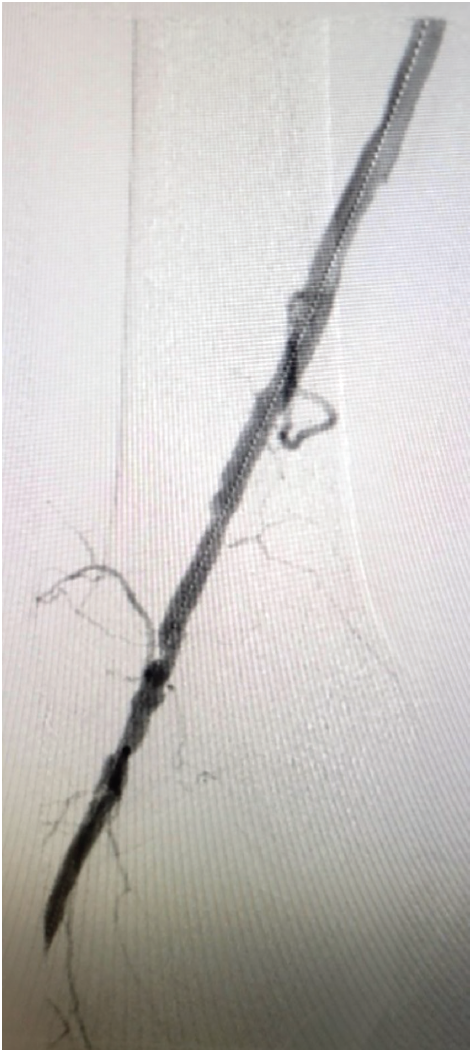

After injecting 2% lidocaine solution into the left groin, a micropuncture system was used in a modified Salinger technique to obtain intravenous-arterial access. A J-wire was inserted through the micropuncture sheath and advanced up to the lower aorta. The micropuncture sheath was removed and replaced by a 5 French (F) sheath. A universal flush catheter was advanced to the level of L1. Abdominal angiography with nonselective renal imaging was performed. After reviewing the images, the catheter was withdrawn to the level of L3. Abdominal angiography with bilateral lower extremity runoff was performed. Due to the aortic stent graft, we were unable to cross over the aortoiliac bifurcation. We obtained right common femoral arterial access, using ultrasound to place a 5F sheath in an antegrade manner. We advanced a Supra Core wire (Abbott) into the total occlusion and the upsized sheath over the Supra Core wire to a 6F, 45 cm Cook sheath. A Glidewire glide catheter (Terumo Interventional Systems) technique was used to traverse the occluded right SFA. The true lumen was reentered distally. Selective angiography confirmed an intraluminal wire position. We exchanged for an .014-inch wire. Laser atherectomy using the 1.5 mm Auryon system (AngioDynamics) was performed in the proximal, mid, and distal right SFA. Several passes were made with the atherectomy catheter on fluency levels of both 50 and 60 mJ/mm2, followed by balloon angioplasty with a 6 mm x 150 mm balloon.

Several prolonged balloon inflations of the proximal, mid, and distal right SFA were performed. There was a residual, >50% stenosis and flow- limiting dissection, so a 6 mm x 200 mm nitinol stent was deployed in the distal right SFA. A 6 mm x 120 mm nitinol stent was deployed proximal to the first stent. The stents were post-dilated with a 6 mm x 100 mm balloon. Selective angiography showed an excellent result. There was no dissection, no thrombus, and improved distal runoff. At that point, all catheters and wires were removed. An Angio-Seal device (Terumo Interventional Systems) was used for closure of the right common femoral arteriotomy site. A ProGlide device (Abbott) was used for closure of the left common femoral arteriotomy site.